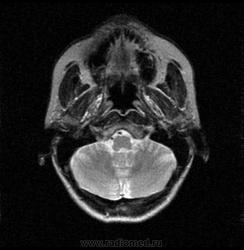

06.06.2011 МРТ - головы и шеи.

Пацентка 36 лет, с жалобами на припухлось в околоушной области справа.

В глубокой доле  правой околоушной железы  на фоне неизмененной паренхимы зона  гетерогенного по Т2, гипоинтенсивного по Т1  с единичными гиперинтенсивными включениями.При контрастировании- накопление контраста диффузное неоднородное и по периферии.Рискну предположить злокачественное образование ( аденокарцинома) с низкой степенью злокачественности( есть капсула, экспансивный рост).Сильно не расстреливайте.

Проблема в том, что перед челюстно-лицевым хирургом стоит распространенность любого объемного процесса, в данном случае все упирается в возмможную травму лицевого нерва и конечно же с дальнейшим его парезом, а ведь женщина  еще молодая. Образование имеет тонкостенную оболочку, по структуре неоднородно, с наличием кальцината, при этом МР-сигнал от окружающих анатомических структур(как костных так и мышечных) не изменен, т.е. об инфильтративном росте речи не идет, в какой то степени доброкачественное. В конкретном случае лицевой нерв с ретромандибулярной веной просто несколько оттеснен.

По гистологии аденома околоушной слюнной железы, но после удаления пока сохраняется парез лицевой мускулатуры, возможно временный.